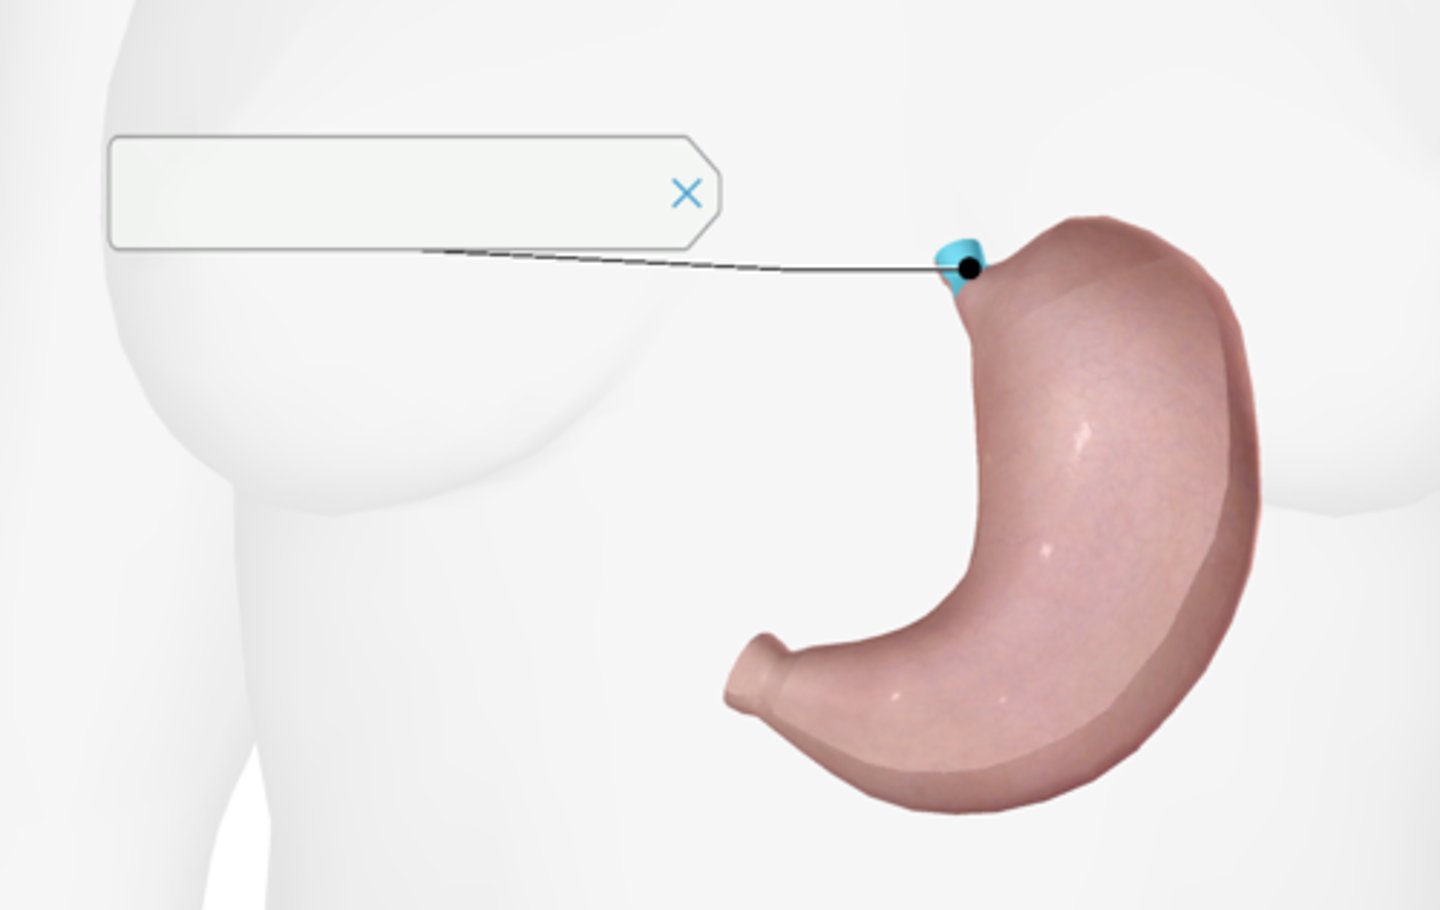

Stomach

Cardiac sphincter